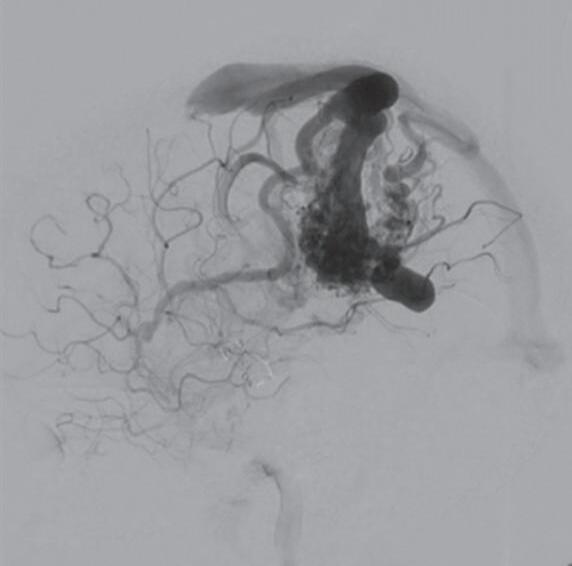

Fig. 1-15. RNM encéfalo T1 (a) sagital sem contraste e (b) axial com contraste demonstrando MAV grau 3, parcialmente embolizada, localizada no giro temporal superior e lobo parietal direito. (c) Arteriografia cerebral em perfil, demonstrando a irrigação pelos ramos da artéria cerebral média e posterior, com drenagem superficial nas veias de Labbé até o seio sigmoide, e o complexo de Trolard no seio sagital superior. O nidus da MAV está demonstrado pelas setas azuis grandes e a drenagem venosa pelas pontas de setas.